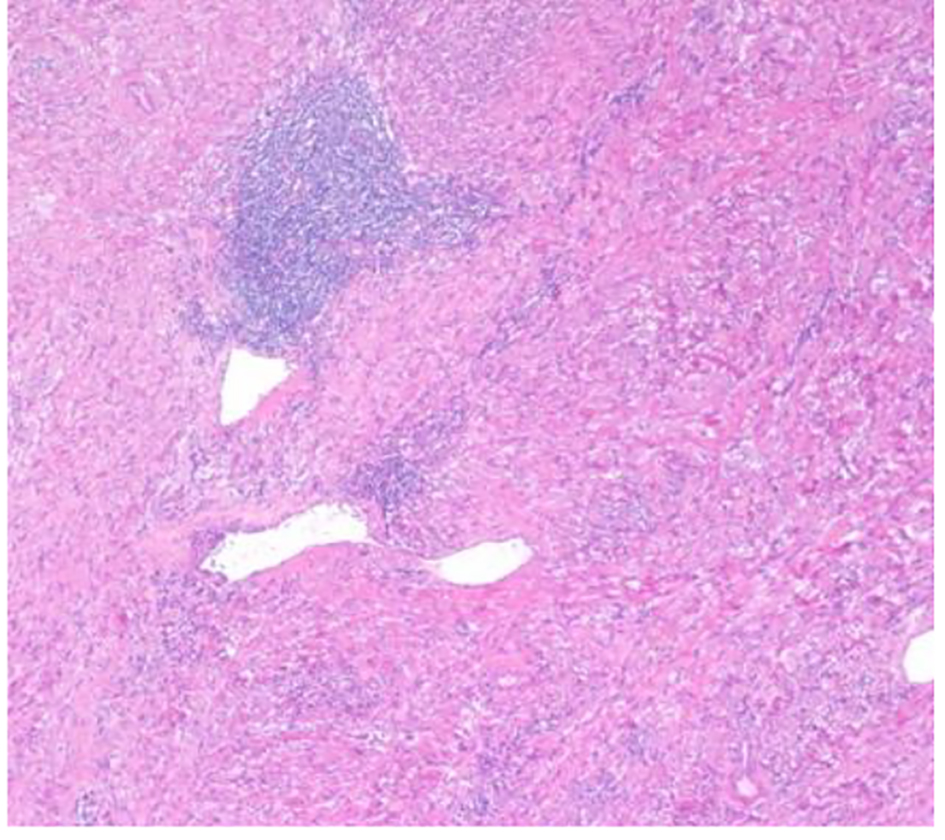

The patient underwent a right adrenalectomy laparoscopic surgery. Pathological evaluation revealed an adrenal schwannoma. Macroscopically tumor was well-circumscribed and encapsulated. The tumor measured 10 × 9.5 × 6 cm and weighed 427 g (Fig. 3). Histopathological findings showed regular fusiform cells, without atypia or mitosis and fibrillar cytoplasm. Intersecting cells were surrounded by histiocytes. Also there was collagen area which was stained with Masson’s trichrome (Fig. 4). Tumor cells expressed S-100 (Fig. 5), IV collagen, vimentin and GFAP. The desmin and c-kit were negative. Ki67 activity was 30%.

![]() Click for large image | Figure 4. Hematoxylin-eosin stain: dense spindle cell proliferation with presence of vascular formations and lymphocytic infiltrates (× 100). |